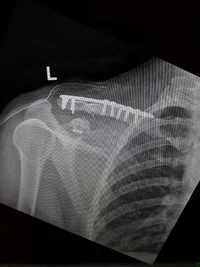

Самый, так сказать, яркий случай произошёл на службе: осколок как-то хитро залетел под броник и расп....расил ключицу, порвав при этом подключичную вену и лишь каким-то непонятным образом не зацепивший одноимённую артерию. Иначе бы наглухо вытек тогда, даром, что находился практически на пороге нашего пвд (пункт временной дислокации).

Думаю, удача больше всего любит два типа людей: смелых и дураков. А я сорвал джекпот, был безбашенным дебилом. ))

Теперь льщу себе мыслью, что стал спокойнее и умнее.. а ещё я немного терминатор и хороший предсказатель погоды: если плечо ноет, то машину мыть рано, скоро опять дождь будет. :51:

А, ну и да, на том осколке моя служба скороптстижно и закончилась, повернув мою жизнь в ту сторону, к которой судьба уже давно подталкивала. Тем шансом я воспользовался.. хоть и не сразу был этому рад. Но сечас счастлив, что перестал упрямиться.